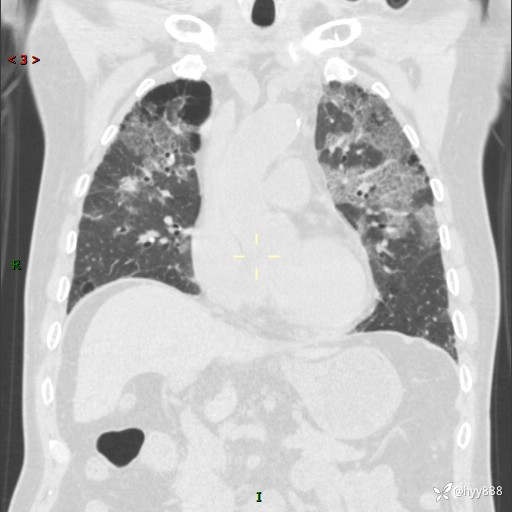

患者性别:男

患者年龄:64岁

简要病史:肝内胆管癌综合治疗后2周余,咳嗽、发热,咳白色泡沫痰。

辅助检查:CT

临床诊断:感染?

讨论:病变性质?